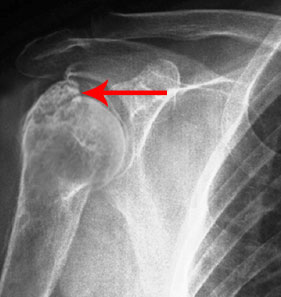

Shoulder Fracture Care

A break in the bone that makes up the shoulder joint is called a shoulder fracture.